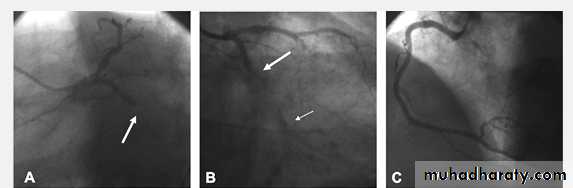

Coronary Angiography

Gold standard to diagnose I.H.D. until nowDemonstrates the anatomy of the artery. By showing

1- severity of stenosis and type of the lesion

a- non-significant stenosis (<70%)

b- Mod or severe (Critical) lesion ( >70% )

2- Extent of the disease:-

single, two ,three vessel disease, Left main

stem disease (> 50%)

3- L.V angiography if done will assess L.V. function

4- If suitable intervention can be done